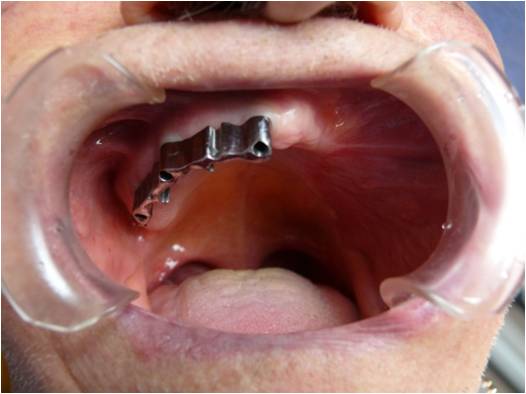

Protesi Sociale

I pazienti parzialmente o completamente edentuli presentano importanti deficit masticatori , fonatori ed estetici .

Presso le nostre sedi è possibile trattare tali casi attraverso l'installazione di protesi rimovibili che ripristinino le arcate dentarie consentendo al soggetto una corretta funzione masticatoria ed una normale vita di relazione.

Nei casi in cui il paziente abbia subìto , per motivi oncologici o chirurgici in generale , una massiva demolizione delle strutture mascellari è disponibile un servizio dedicato di terapia implantoprotesica allo scopo di ristabilire le adeguate funzioni cui il cavo orale è predisposto cercando di limitare il piu' possibile i deficit sopraggiunti.

![]() | ![]() |